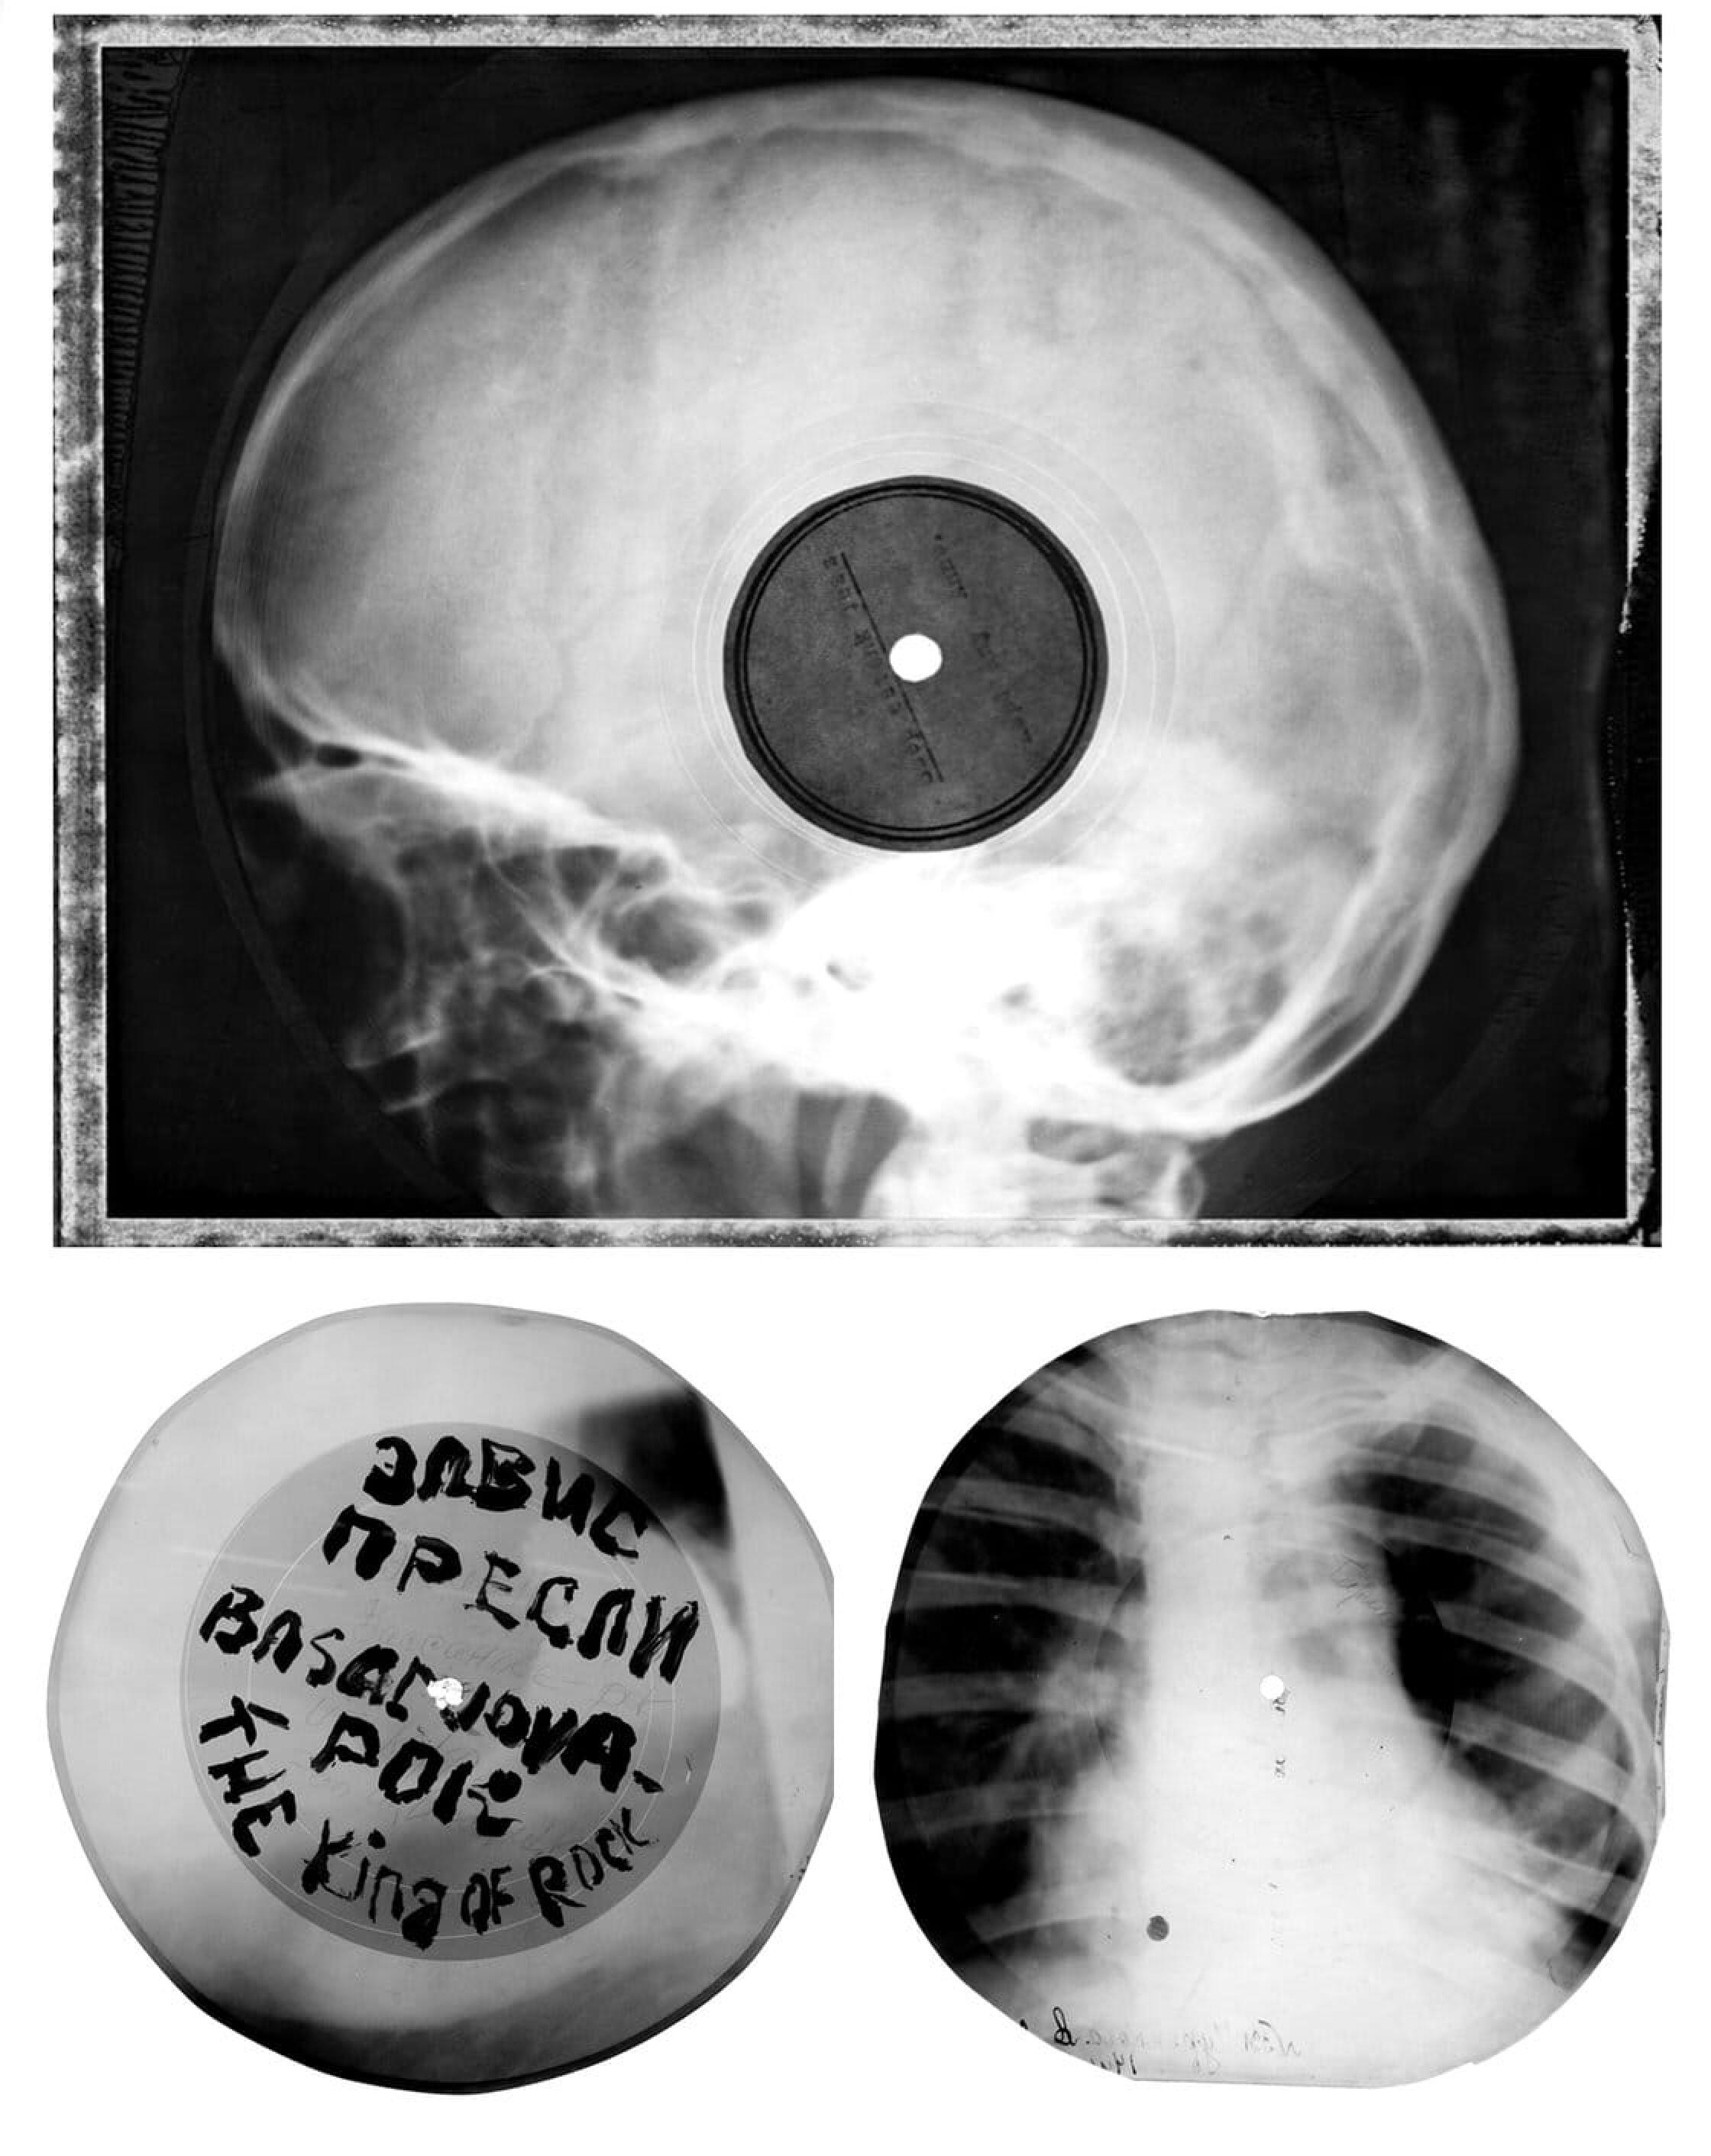

En URSS, les amateurs de jazz et de rock pressaient leurs disques sur des radiographies.

Ils se servent en effet d’anciennes radio pour presser la musique : les zazous de l’époque (qu’on appelle stiliaguis) volaient ainsi les radiographies dans les hôpitaux, et gravaient grâce à des phonographes et en trouant les radios avec une cigarette ce que l’on appelle des « Bones ». Ainsi, avec Elvis sur le poumon, Duke entre les côtes, la musique pouvait circuler en très mauvaise qualité mais à un prix dix fois inférieur à celui des marchés occidentaux. Aujourd’hui, il reste de cette période ces radios qui sont presque de véritables oeuvres d’art.